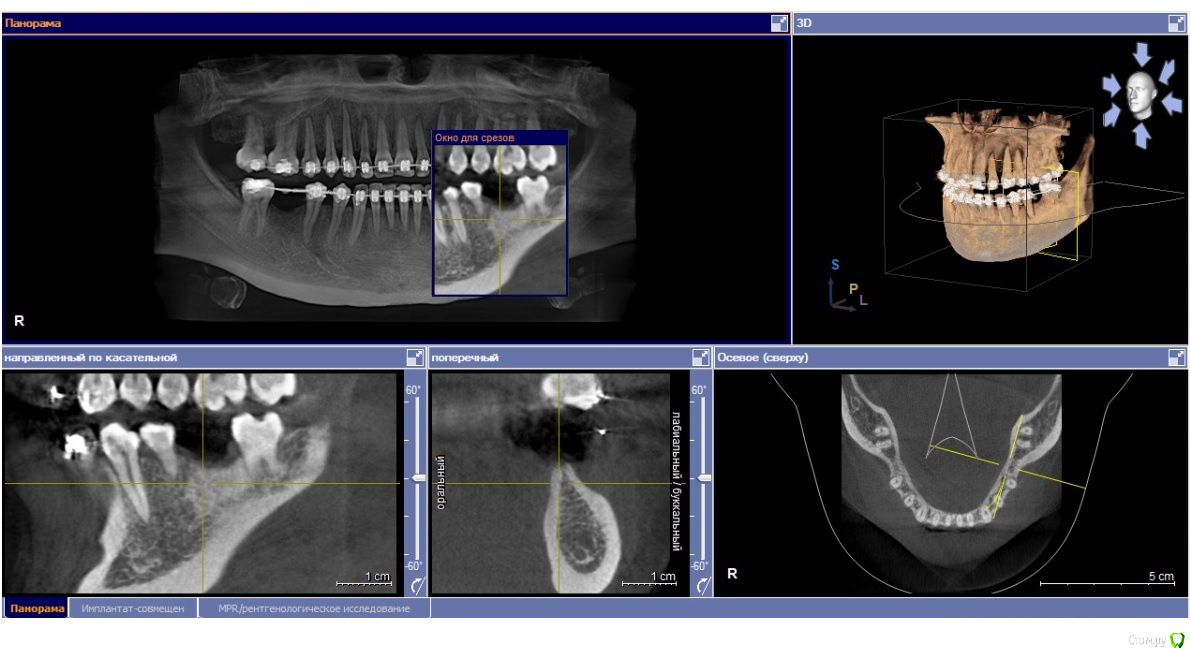

my_evid Опубликовано 15 ноября, 2019 Поделиться Опубликовано 15 ноября, 2019 Здравствуйте! Прошу высказать свое профессиональное мнение на мою ситуацию. Заканчиваю ортодонтическое лечение, 15 лет отсутствуют 46 и 36, мне сообщили о необходимости установки имплантов для дальнейшего сохранения результата. В итоге у трех хирургов разное мнение на этот счет: 1. необходима костная пластика по бокам и под имплантатом (с установкой костного блока) (вроде)2. костная пластика необходима по бокам3. костная пластика не нужна. Как мне объяснил врач, придерживающийся третьего варианта, костная пластика необходима в моем случае для того чтобы коронка была одинакового размера с остальными зубами, это важно только для эстетики, на жевательную способность это не влияет, а так, есть возможность имплантат вогнать глубже и обойтись без этой операции.Врач, придерживающийся второго варианта, сказал что тоже сделаем глубже имплантат, коронки будут отличаться по высоте, но пластика нужна по бокам, как я поняла, непосредственно для его установки.Так как это дополнительные средства и дополнительное вмешательство, не знаю как поступить. Сделала скрин КТ, надеюсь что-то будет ясно. Ссылка на комментарий

Irouil Опубликовано 15 ноября, 2019 Поделиться Опубликовано 15 ноября, 2019 Надо замеры делать на кт, но, на первый взгляд, возможны два последних, из перечисленных Вами, варианта, первый кажется чрезмерным Ссылка на комментарий